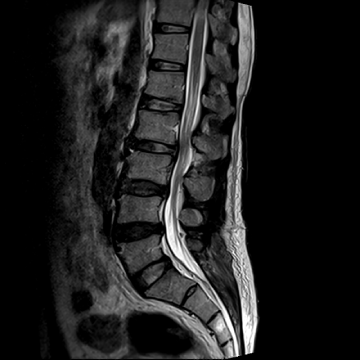

허리 디스크 수술 전·후

2022.09.05

2022.09.08

ㆍ환자 동의를 받은 자료이며, 이미지 사진은 실물과 다를 수 있습니다.

ㆍ모든 자료는 새움병원 자료입니다.